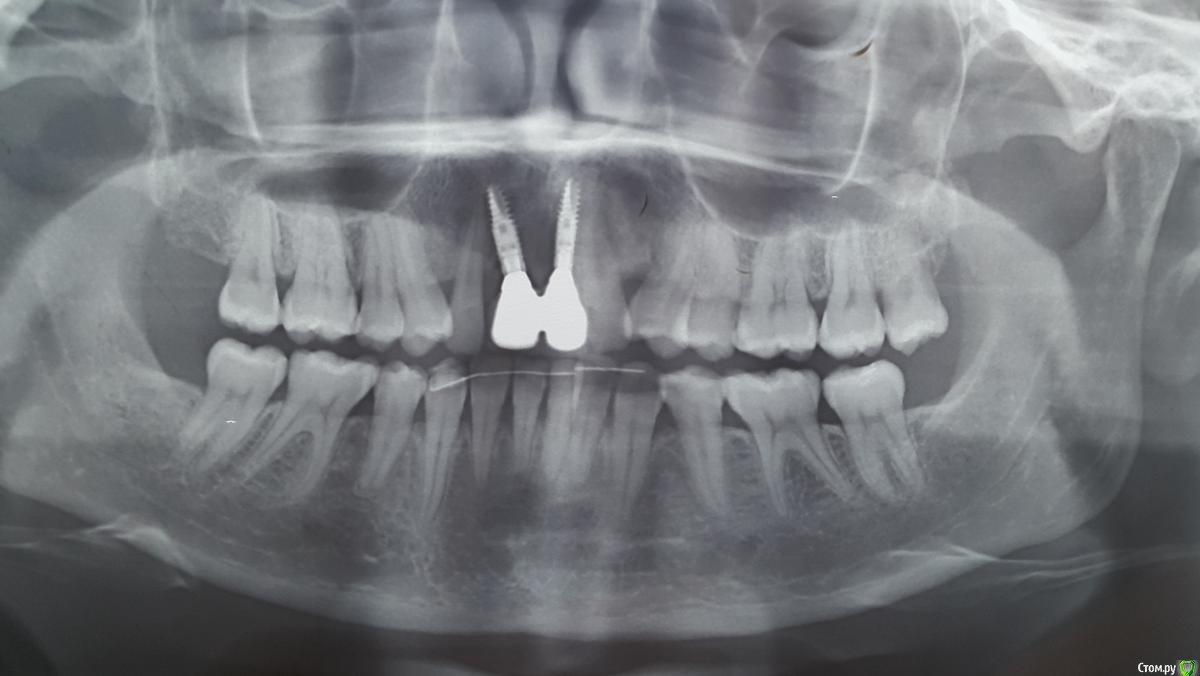

Lady-Kisa Опубликовано 31 марта, 2018 Поделиться Опубликовано 31 марта, 2018 Добрый день! Подскажите пожалуста правильное ли положение у моих имплантов Densply 3,0?Проблема в том, что 2 раза уже ломались абатменты из диоксида циркония.Один врач говорит, что дело в положении имплантов (криво установлены) нужно заново делать имплантацию.Другой говорит решение проблемы - поставить титановые абатменты и ломаться ничего не будет.Боюсь снова выкинуть деньги на ветер. Ссылка на комментарий

krokomot Опубликовано 1 апреля, 2018 Поделиться Опубликовано 1 апреля, 2018 По снимку я бы предположил, что протребуется повторное ортодонтическое лечение, но вам же не нужны предположения, для достоверной оценки требуется сделать то что написал коллега выше. Ссылка на комментарий

Bier Опубликовано 2 апреля, 2018 Поделиться Опубликовано 2 апреля, 2018 титановые скорее всего не сломаются Ссылка на комментарий